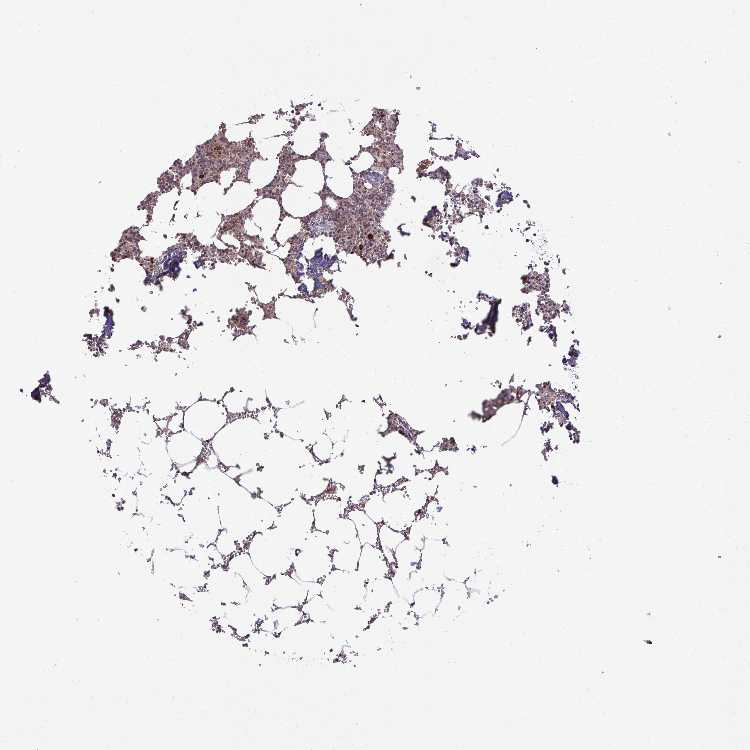

BONE MARROW - Antibody stainingi

Antibody staining in the annotated cell types in the current human tissue is reported as not detected, low, medium, or high, based on conventional immunohistochemistry profiling in selected tissues. This score is based on the combination of the staining intensity and fraction of stained cells.

Each image is clickable and will lead to virtual microscopy that enables deeper exploration of all samples and also displays staining intensity scores, fraction scores and subcellular localization as well as patient and tissue information for each sample.

Antibody HPA054512Antibody HPA059951

Hematopoietic cells MediumLow